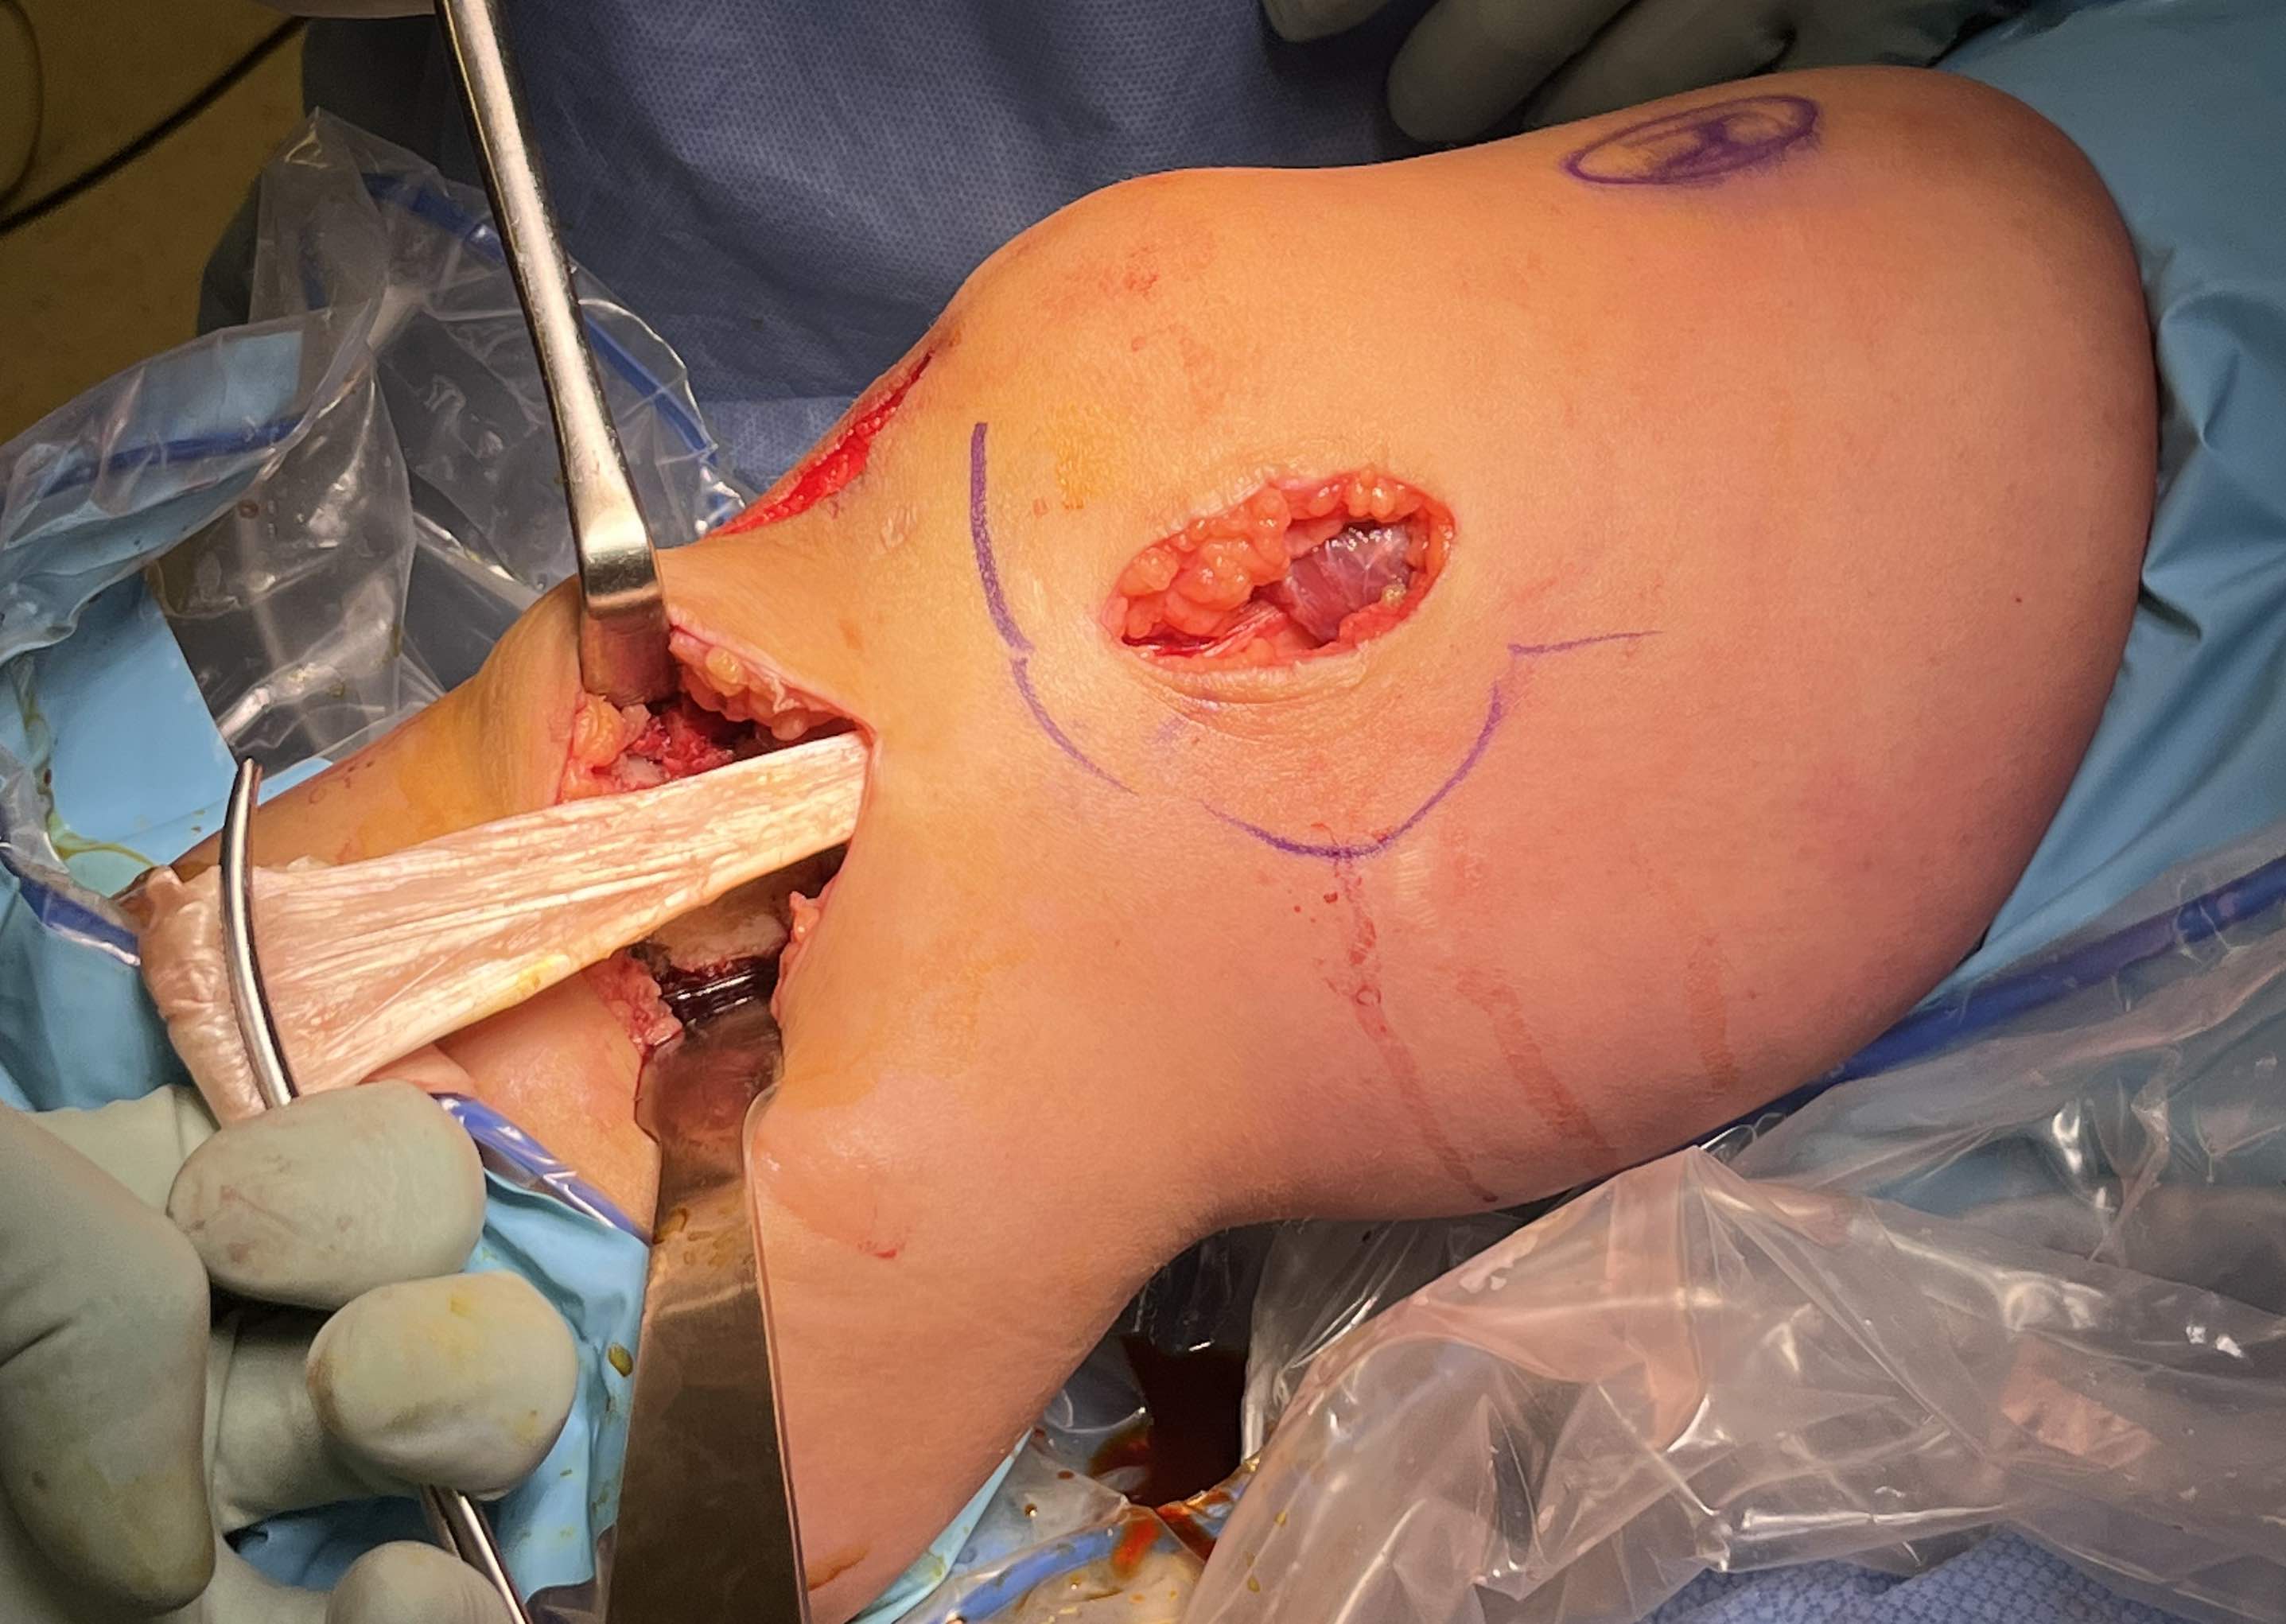

3. Reconstruction of MCL and posteromedial corner

A. Single bundle anatomic allograft MCL reconstruction (no POL)

Femoral attachment

- 4 mm proximal and posterior to medial epicondyle

- image intensifier: intersection of the posterior femoral condyle with Blumensaat's line

- 40o anterior to avoid notch

- 40o proximal to avoid PCL tunnel

Tibial attachment

- 6 cm from joint line

- just posterior to pes attachment

B. Single bundle anatomic hamstring autograft MCL reconstruction (no POL)

C. Double bundle anatomic reconstruction of MCL and POL

Surgical Approach to Medial Knee

Position

- knee flexed to 90o, over bolster

- tourniquet

- sandbag under hip

Incision

- hockey stick medial incision

- halfway between borders of tibia

- extends proximally to adductor tubercle

- distally to pes anserinus

Superficial dissection

- protect the saphenous nerve and small saphenous vein

- emerges from between sartorius and gracilis

- divide medial patella retinaculum from VMO down

- divide sarfascia over pes anserinus

- reflect pes anserinus inferiorly

Deep dissection

- elevate VMO to identify proximal insertion of superficial MCL

- expose superficial MCL running from medial epicondyle down to tibia under pes

- popliteal oblique ligament and semimembranosus are posterior to MCL

- can expose posterior capsule by carefully reflecting medial gastrocnemius posteriorly